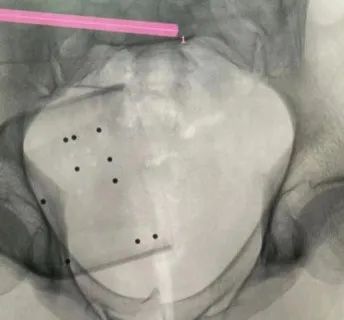

机器人完成患者信息二维图像采集后设计出螺钉置入方向

患者37岁,为高坠伤患者,入院合并颅脑挫伤、盆腔脏器出血、骨盆骨折多发伤患者。为最大限度降低手术风险,同时给予患者满意的手术疗效,术前综合评估患者病情,拟定行“天玑机器人”辅助定位下骨盆骨折微创手术。2月13日10时,手术正式开始。拉萨市人民医院采集患者术中二维影像,通过骨科手术机器人拟定螺钉打入位置方向后,吴宏华主任完成手术设计,成功为该患者置入了一颗高难度骶髂螺钉,出血5ml,切口1cm。术后图像显示,螺钉位置及方向完全符合手术规划,没有一丝偏差,手术成功。